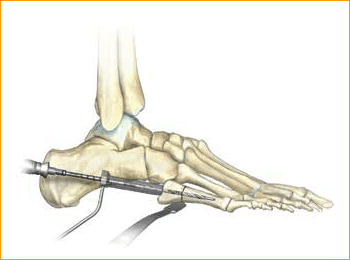

Jones Fracture Technique for 4.5 mm and 5.5 mm Headless Compression screws.

8. FRACTURE COMPRESSION

In order to account for countersinking and fracture compression, a screw that measures 5 mm shorter than the measured total depth is inserted over the guide wire while protecting the soft tissues with a soft tissue guide.

9. SCREW INSERTION

The screw is placed while under fluoroscopic guidance in order to avoid cortical penetration. Postoperative protocol: The patient is placed into a soft dressing, supported by a fiberglass splint. Patients can be made non-weight-bearing for a period of 2–6 weeks postoperatively depending upon Torg type of fracture, bone quality, and underlying morbidities.